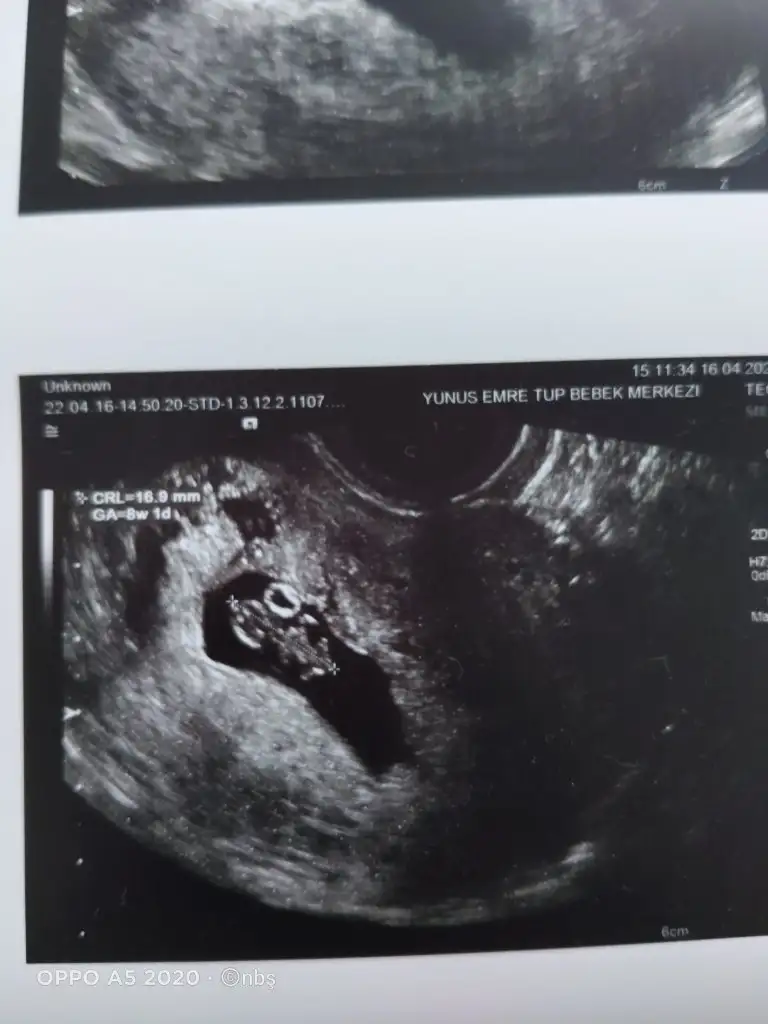

• IMG20220416130628.webp

IMG20220416130628.webp

24,9 KB · Görüntüleme: 93